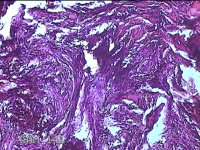

左肩背部结节

性别

男

年龄

27岁

临床诊断

皮脂腺囊肿

一般病史

发现左肩背部结节1个月余,无明显疼痛及不适。

标本名称

大体所见

灰白暗红色带皮肤样结节1.3x0.8x0.3cm一个,表面糜烂,切开结节呈实性,切面灰白暗红色,质中。